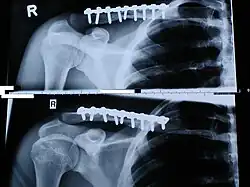

Plattenosteosynthese

Bei der häufig angewendeten Operationsmethode der Plattenosteosynthese wird der Bruch mit einer Platte und Schrauben sowie zweier interfragmentär verankerten Zugschrauben stabilisiert. Die Platte wird wegen des hohen Refrakturrisikos nach frühestens eineinhalb bis zwei Jahren entfernt.[1]

Als Weiterentwicklung der herkömmlichen Platten werden inzwischen spezielle an die Schlüsselbeinanatomie angepasste flache (low profile) und winkelstabile Platten (Locking Compression Plates, kurz: LCP) benutzt, mit denen die anatomische Position des Schlüsselbeins bei der Operation genau eingestellt (Osteosynthese) und während der gesamten Heilungsdauer gehalten werden kann.[19]

Winkelstabile Platten enthalten neben ovalen Löchern einzelne Löcher mit einem zusätzlichen Gewinde, um die Schrauben winkelstabil zu verankern.[11][9] Durch oval geformte Löcher der Platte können die Schrauben leicht gekippt im Knochen verankert werden. Insgesamt wird im Unterschied zu herkömmlichen Platten eine Stabilität der Platte im Knochen erreicht, ohne dass die Knochenhaut durch den Druck der Platte zerstört wird.[19][9]